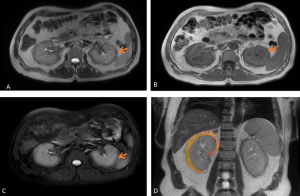

RPF is typically hypointense on T1-weighted images with variable intensity on T2-weighted images as well as in apparent diffusion coefficient values depending on the degree of active inflammation [2,3].